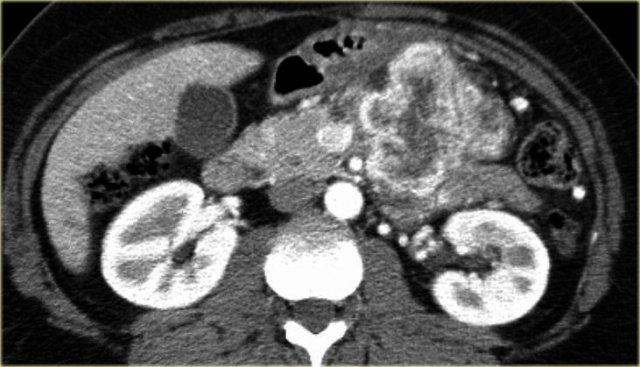

Hình ảnh CT của bệnh nhân nữ 32 tuổi với triệu chứng đau vùng thượng vị trái lan ra sau lưng.

Ghi nhận một nang lớn ở đuôi tụy có vôi hóa ngoại vi.

Có vách ngăn mờ nhạt như thấy trên hình bên trái và thành nang dày.

Có thể cần phóng to hình ảnh để quan sát rõ vách ngăn.

Có thể đưa ra chẩn đoán đặc hiệu là MCN.

Hình ảnh CT của bệnh nhân nữ 46 tuổi với triệu chứng đau bụng phải mơ hồ.

Các đặc điểm hình ảnh bao gồm:

- Nang có vách ngăn kích thước 7 cm ở đầu tụy.

- Vỏ nang nhẵn.

- Không có thùy hóa (lobulation).

- Không thông với ống tụy chính.

MRI cho thấy nang có vách ngăn ở đầu tụy kích thước 7 cm với vỏ nang nhẵn, không có thùy hóa và không thông với ống tụy chính.

Kết quả phẫu thuật xác nhận u nang tuyến nhầy độ thấp (low grade mucinous cystadenoma) có mô đệm buồng trứng (ovarian stroma).